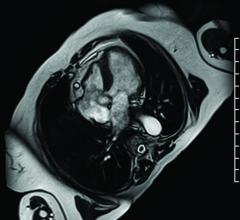

May 10, 2016 — Imricor Medical Systems announced enrollment of the first patients in a clinical study to evaluate the ...

May 10, 2016 — Cardiovascular magnetic resonance (CMR) is a stronger predictor of risk for major adverse cardiovascular ...